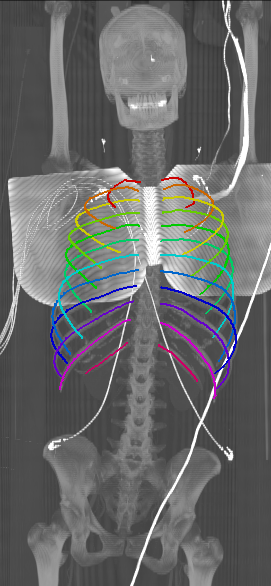

With an average Euclidean distance error of 0.787 mm, we obtained an overall result that is generally better compared to what is reported in the state of the art. Although, it needs to be kept in mind that results are unfortunately not directly comparable as both the data sets as well the evaluation metrics significantly differ across prior work. Similarly to the results obtained on the probability maps, distance errors are significantly higher for first and twelfth rib compared to the rest of the rib cage. As discussed, this is caused by the intrinsic challenges of these ribs, but certainly also an affect of error propagation in that sense that the quality of the probability maps also impacts centerline extraction. Interestingly, the right ribs are generally slightly worse compared to the left ribs, probably due to a slightly unbalanced data set with more challenges on the right side. Figure 5 shows the centerlines which were automatically generated using our walker algorithm from the corresponding network outputs displayed in Figure 4.

Refer to caption

Figure 5: Automatically generated centerline splines associated with the FCNN outputs displayed in Figure 4. The selected case above display common difficulties which are inherent in the data set, such as pads (a) or cables (b), internal devices such as pacemakers (c), stents (d), spinal (e) and femural/humeral implants (f), injected contrast agents (g), patient shape variations such as scoliosis (h), limited field of views (FOVs), i.e. partly missing first (i) or twelfth rib (j).